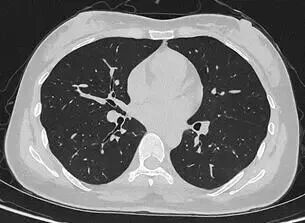

联影uCT Ultima扫描的0.2mm肺部超高清成像,扫描剂量低至0.1mSv

目前,华西厦门医院已基于该设备完成第一批患者扫描。“光子计数能谱CT的临床落地,是我国创新能力的重要体现。光子计数能谱CT实现了大幅降低辐射剂量,让患者CT扫描更安全。”华西厦门医院党委书记廖志林说,“我们在临床案例中看到,设备不仅低剂量且高清,肺结节依然清晰可辨,临床价值十分突出。设备将在华西厦门医院的全链条、全生命周期的健康管理服务中发挥重要作用。”